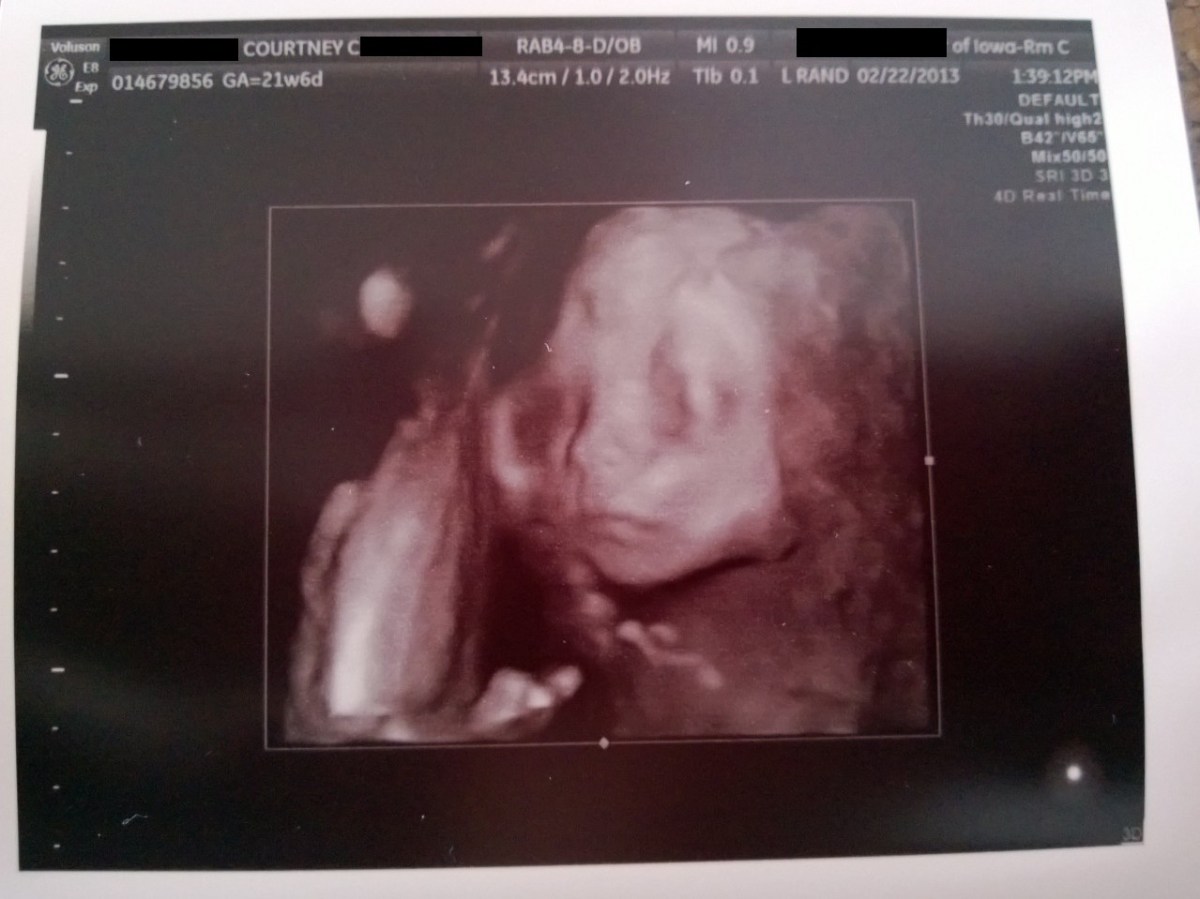

WP_20130222_006 February 22, 2013 by Courtney Leave a comment ← Previous Image Next Image → 21w6d – I think this one may look like me! Like Loading...